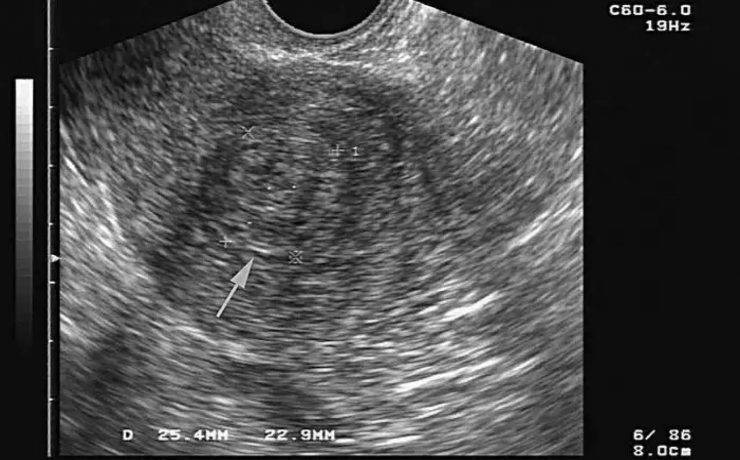

EL MODO A (modo de amplitud) fue el primer método utilizado para formar imágenes de ultrasonido. EL MODO B: modo de brillantez MODO M: modo de movimiento. Tiene su utilidad principal en ecocardiografía tanto en la fetal como en la del adulto. MODO B.- imagen en tiempo real. Al mover